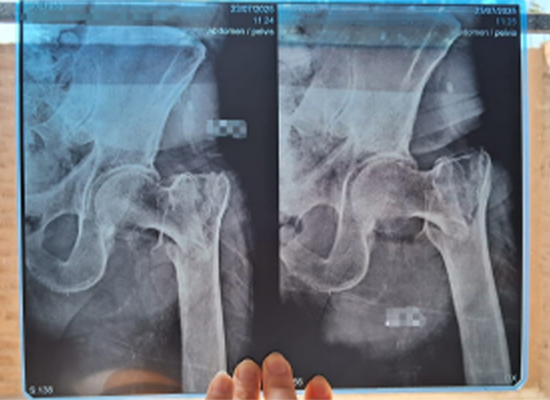

L'imagerie radiographique a confirmé une fracture intertrochantérienne gauche déplacée , nécessitant une intervention chirurgicale rapide pour restaurer la stabilité et la mobilité.

Radiographie préopératoire montrant une fracture intertrochantérienne gauche déplacée chez un patient âgé, Lima Pérou